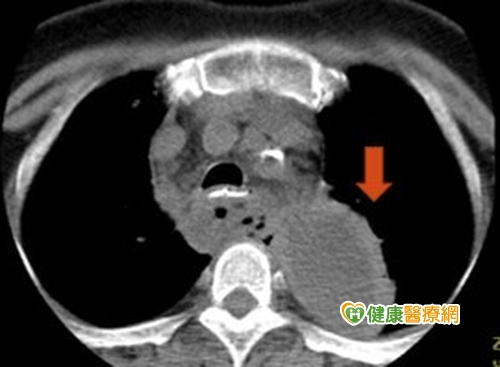

罕見原發性縱隔腔膿瘍 糖尿病患易好發

1名60歲婦人,原有第二型糖尿病史,因發生輕微車禍後,緊急就醫,起初僅出現左上胸背處疼痛,直到後來合併發燒,才進一步接受檢查,醫師發現胸部影像出現突出腫塊,且約有10公分大小,但食道周圍也無任何破裂情況,確診為罕見的原發性上後縱膈腔膿瘍。